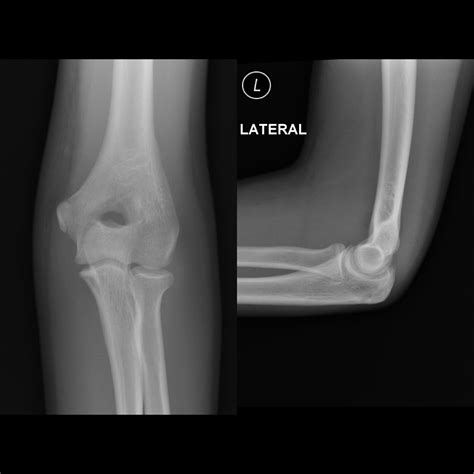

Doctors will typically use X-rays to visualize the bones and confirm a diagnosis. In more complex cases, such as intra-articular fractures, a CT scan might be required to determine if surgical intervention is necessary to realign the bone fragments.

- broken elbow pictures